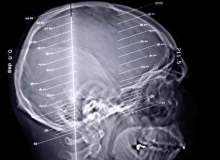

Hafif felç geçici iskemik atak, kısaca GİA olarak adlandırılır. Hafif felç, felçle aynı nedenlerden kaynaklanır ve aynı belirtileri gösterir, ama o kadar uzun sürmez ve beyin hasarıyla sonuçlanmaz. GİA, vücudunuzun size, felç tehlikesi altında olduğu